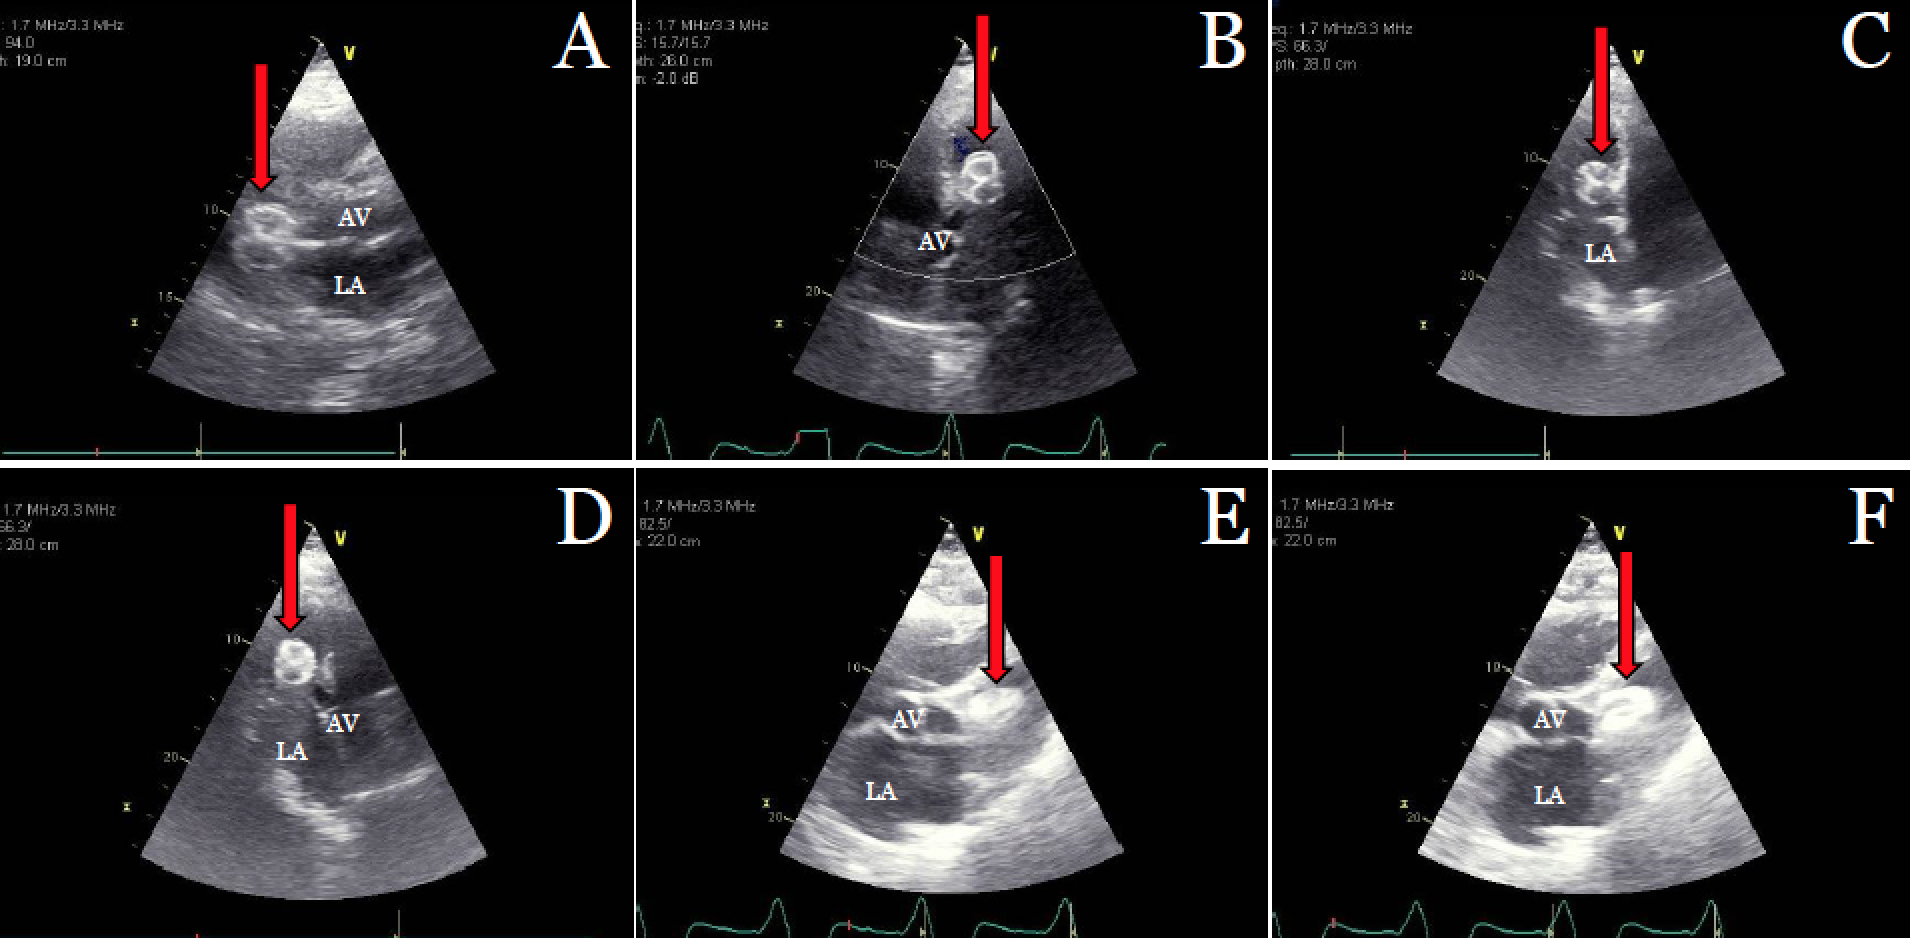

An 80-year-old man with AF and mitral valve prolapse status post MitraClip presented to the hospital for difficulty breathing and palpitations two days after implantation of a 31mm Amplatzer Amulet LAAO device. Notably, he underwent failed attempt at Watchman LAAO implantation due to peridevice leak one year prior. On arrival, he was hypotensive with numerous episodes of polymorphic VT, requiring cardioversion, vasopressors, and mechanical ventilation. TTE located the Amulet within the LV outflow tract (LVOT) creating LVOT obstruction and revealed single-leaflet attachment of the MitraClip. He was evaluated for device retrieval and mechanical support but was deemed not a surgical candidate due to severe thrombocytopenia and guarded prognosis. Despite ongoing resuscitative efforts, the patient became increasingly unstable and died in the cardiac ICU.

In patients who are unable to tolerate OAC, occlusion of the LAA for stroke prevention has garnered growing interest; however, these devices are not without complication and do not guarantee full occlusion of the LAA. Despite our patient’s history of failing Watchman deployment, he was discharged on the same day after implant of the Amulet device without post-procedure TTE. We postulate that the Amulet device dislodged shortly after deployment and was held within the left atrium by the MitraClip until detachment, allowing for device embolization and severe MR. To our knowledge this is the first documented instance of Amulet device migration into the LV in a patient with a MitraClip. This case highlights the need for heightened post-procedure monitoring, surveillance, and imaging in select patients.